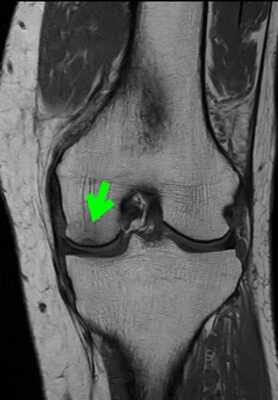

MRIで何が分かるの?

MRIでは、レントゲンでは分かりにくい

「骨の中の傷み(むくみのように見える変化)」を確認できます。

「痛みの原因がここにある」という判断がしやすくなり、治療方針が立てやすくなります。

【初診時MRI画像】

膝の内側に“骨の傷み(骨の損傷・炎症を起こしている部分)”が確認できます。

骨壊死を起こしている部分が確認できます